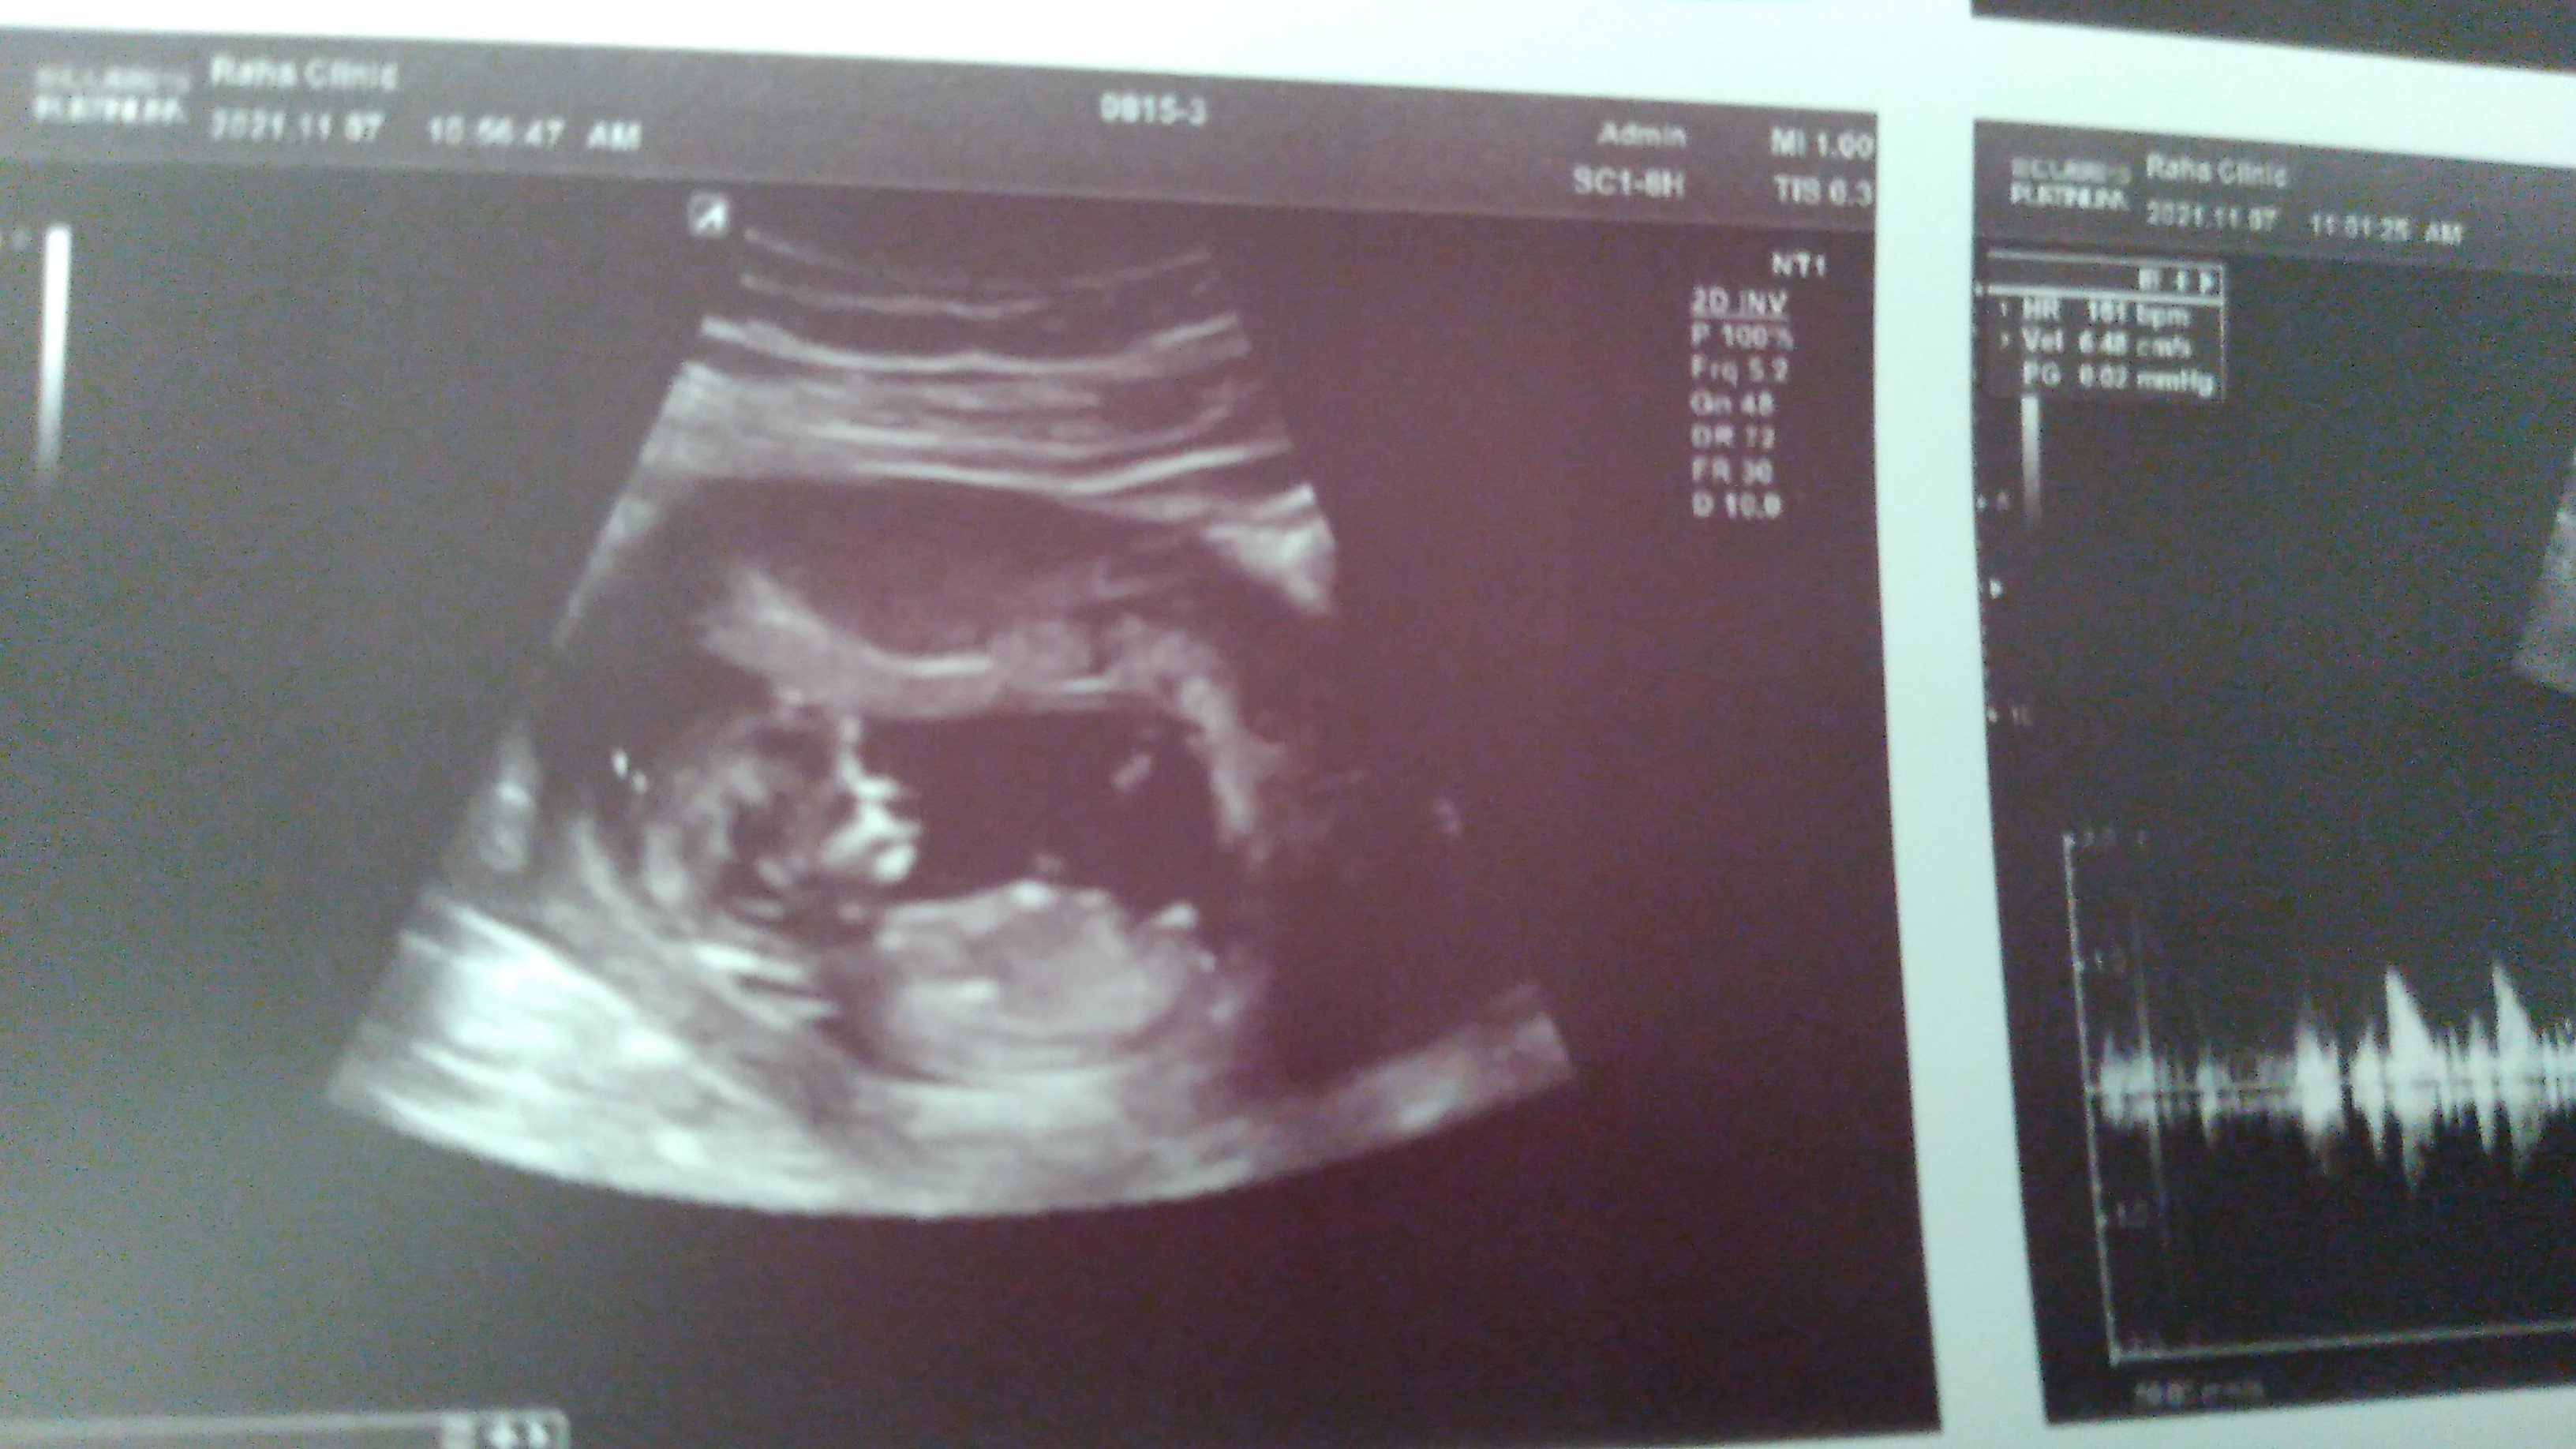

تعیین جنسیت از روی سونو ان تی

عکسشو میذارم ببینید میتونید تشخیص بدین؟